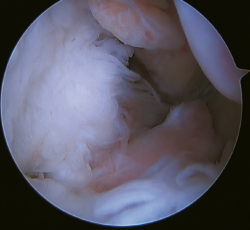

La principal indicación de esta reparación es la rotura del fascículo superior del LTFA de su inserción fibular, presentando una buena calidad tisular del remanente de ligamento (Figura 3).

Figura 3. A: identificación de la inserción fibular del LTFA (*) con excelente calidad del remanente tisular; B: técnica con dos implantes sin nudos y a través de un portal anterolateral único modificado; C: resultado final. P: peroné; T1: túnel talofibular; T2: túnel calcaneofibular.